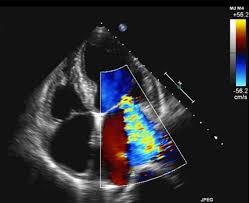

One interesting thing was that before the surgery, they weren't entirely sure whether they were going to be repairing the tricuspid valve. So the anesthesiologist did an echo by sliding a probe into the patient, near the patient's heart, and rotating the probe to look at the different valves on a screen. He could also turn on a blood flow feature, which showed us different colors, each color illustrating a different blood velocity. This allowed us to see whether there was regurgitation, aka "regurg," which there was, from all three valves in question. (The image of a heart echo above shows mitral regurgitation, or blood flowing in the wrong direction, similar to what this patient had.)